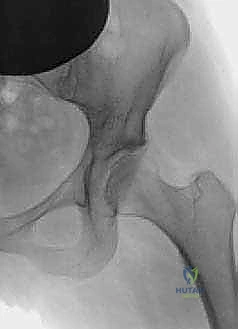

2. الأشعة السينية (X-rays): بأوضاع محددة لقياس زوايا التغطية (مثل زاوية CE وزاوية Tönnis) وتحديد درجة خلل التنسج.

3. التصوير بالرنين المغناطيسي (MRI / MRA): لتقييم حالة الغضروف المفصلي والشفا الحُقي. إذا كان الغضروف متآكلاً بشكل كامل (خشونة متقدمة)، فإن جراحة PAO قد لا تكون مجدية، ويكون استبدال المفصل هو الحل الأفضل.

4. الأشعة المقطعية ثلاثية الأبعاد (3D CT Scan): تُستخدم للتخطيط الجراحي الدقيق قبل العملية.

بعد تحرير التجويف، يقوم الدكتور هطيف بتدويره في ثلاثة أبعاد (3D) ليغطي رأس عظمة الفخذ بشكل مثالي. يتم التحقق من التغطية الجديدة باستخدام جهاز الأشعة السينية الفلوروسكوبي داخل غرفة العمليات لضمان الزوايا المثالية.